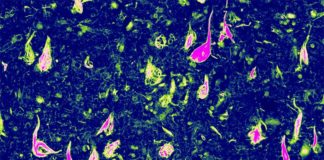

Tanto las personas jóvenes como las de edad avanzada tienen un menor grado de neuroinflamación (rojo) que los pacientes con enfermedad de Alzheimer

Imagen microscópica confocal de microglía (verde) que envuelve placas de amiloide (azul) en el Alzheimer